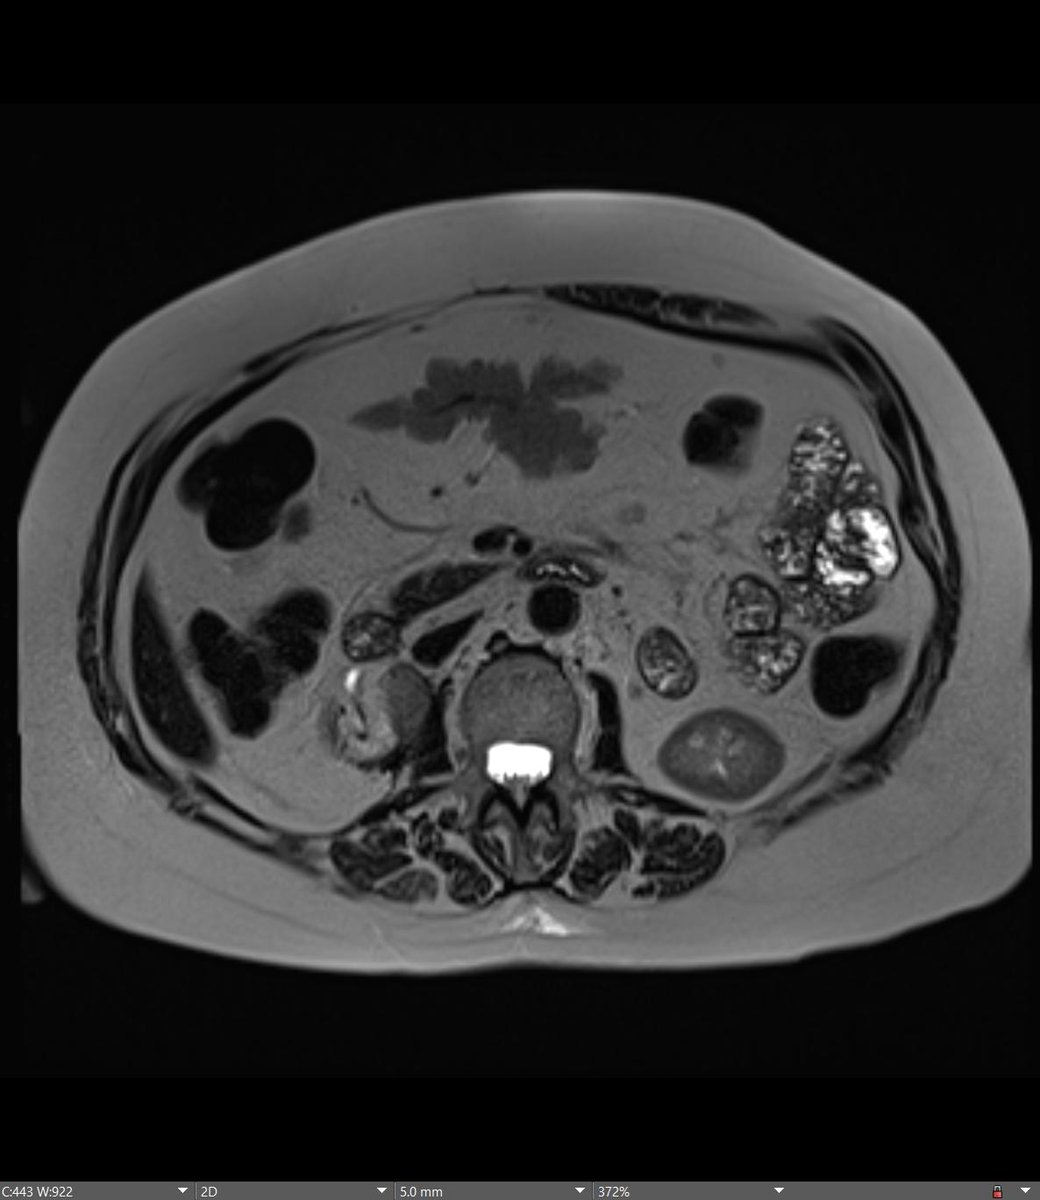

60-year-old male patient with history of cirrhosis undergoes HCC screening with non contrast MRI (patient refuses IV gadolinium due to hives)... Diagnosis? Next step? @BrighamRad @FOAMrad @SAR_RFS @futureradres @ARRS_Radiology @Abdominal_Rad @CBRadiologia #MedEd

All right, all right... Where is the spleen? This patient is status post splenectomy for trauma. MRI performed 5 years later confirming benign vs indolent etiology... this is... Mesenteric SPLENOSIS! @BrighamRad @FOAMrad @SAR_RFS @futureradres @ARRS_Radiology @Abdominal_Rad